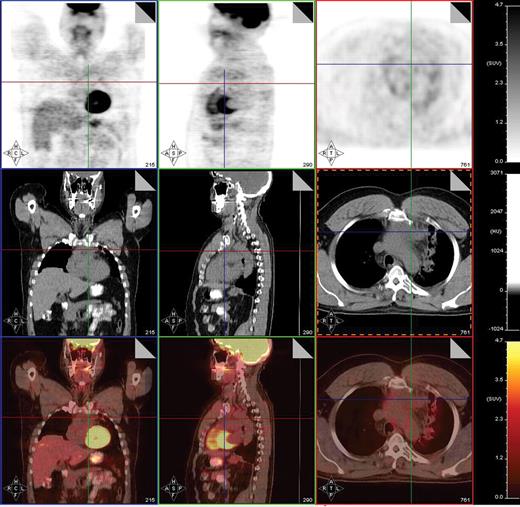

PET-positive residual mass in the anterior mediastinum extending into the left supraclavicular region in a patient with nodular sclerosis Hodgkin lymphoma. This patient underwent a restaging PET/CT scan 2 months following treatment with 6 cycles of ABVD. Fused PET/CT images show that the residual mass uptake is clearly greater than that of mediastinal blood pool structures, consistent with persistent disease. This was confirmed by fine needle aspiration and the patient then underwent salvage chemotherapy.